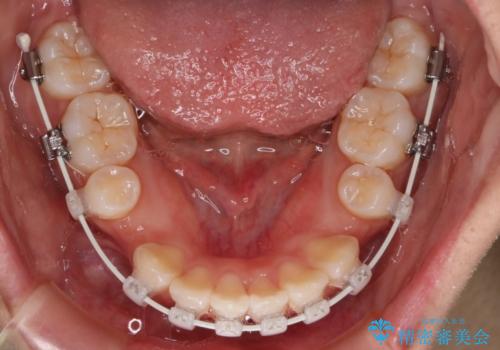

- 矯正装置

- 審美装置

- 治療期間

- 1年9ヶ月